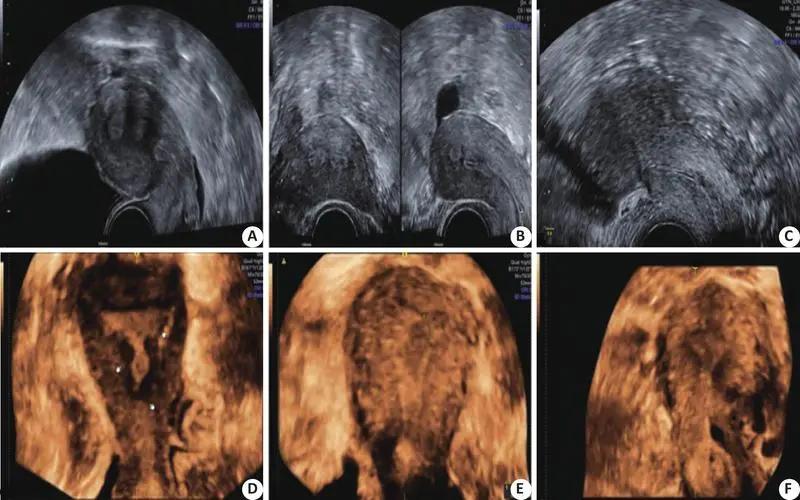

常规超声是目前诊断肾脏囊性占位性病变的首选方法,但对准确判断肿块性质仍存在一定困难, 因此常需进一步做增强CT或MRI进行定性诊断,但增强CT及MRI对一些内部有出血坏死、囊性变或乏血供的肾脏肿瘤与小良性肿瘤鉴别困难。

超声造影是一种新型的诊断技术,能够清晰、准确的显示病变组织的血流状况,有助于提高诊断准确率。

有文献报道CT与MRI对于CRM的诊断分类是一致的,超声造影则有助于提高CRM的诊断准确率常规超声是CEM的首选影像学检查方法,可以敏感地检出肾脏局灶性病变。

但常规超声诊断效果单一,只能够探查囊肿病变组织的形状、大小以及内部回声等基本指标,但由于不能准确显示血供,因此无法精确判断CRM的良恶性。

超声造影(contrast-enhancedultrasound,CEUS)是一种新型的增强影像学检查技术,不仅能够有效增强患者肾脏的超声影像和血流多普勒信号,也能够准确反映出病变组织的血流灌注情况。

对恶性囊性病变不规则增厚的囊壁、囊壁结节及囊内的实性和囊性成分的勾画很清晰,同时造影剂可停留在血管腔内,不会被肾小管排出,无肾毒性, 是理想的肾脏病灶影像学诊断手段之一。

另外,研究报道CEUS诊断多囊性肾癌的阳性预测值为77.8%,阴性预测值为80.0%,为治疗方式的选择提供较为可靠的依据。 在肾囊性占位性病变的诊断上,CEUS较增强CT更有优势。

研究发现CEUS诊断囊性肾癌的准确率优于CT,其原因在于超声造影剂可在分隔、囊壁以及囊内实性成分内的微小血管中显示,从而更易于观察病变的特点。

而CT存在部分容积效应, 即使高分辨CT有时也很难分辨分隔,一些较小的囊内实性成分在增强CT上的增强程度不如CEUS, 因此临床中会出现增强CT在判断Bosniak1II、IV级的囊性占位存在困难;

我国学者比较103例肾囊性占位性病变患者行超声造影、增强CT及传统超声诊断价值,结果发现CEUS对病灶囊壁、分隔或实性成分的诊断效能明显优于传统超声和增强CT检查。